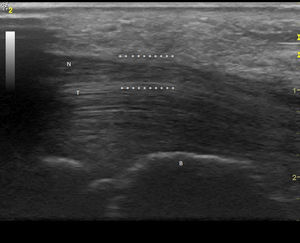

Observación clínicaMujer de 84 años, hipertensa controlada, presentaba desde hace 2 meses lesiones cutáneas en ambas manos de tipo vasculítico asociadas a cianosis del 1.er, 2.° y 3.° dedos, y a dolor intenso que motivaron hospitalización en urgencia por sospecha de vasculitis sistémica. En la anamnesis dirigida, no había elementos de conectivopatía ni consumo de drogas. Recibía enalapril para tratar su hipertensión arterial. En el examen físico destacaban lesiones periungueales, en pulpejos, indicativas de vasculitis, pero llamaba la atención su distribución dermatómica, la severa hipoestesia asociada en el mismo territorio y la importante atrofia de la eminencia tenar, de manera bilateral (fig. 1). El resto del examen era normal; en particular, no había lesiones cutáneas en otras localizaciones y su tensión arterial era normal. Se realizó estudio: hemograma y velocidad eritrocitaria de sedimentación normales, función renal y orina completa normales, factor reumatoideo negativo, anticuerpos antinucleares negativos, perfil ENA detallado negativo, ANCA c y p negativos. La paciente refería de alteraciones de la sensibilidad con parestesias nocturnas y falta de fuerza en manos con tiempo de evolución prolongado, por lo que ya había consultado. Se había hecho el diagnóstico de STC, realizándose una electromiografía de extremidades superiores un año antes. Esta mostraba ya un severo atrapamiento de ambos nervios medianos a nivel de los túneles carpianos, con denervación completa de las eminencias tenares. Se realizó estudio ultrasonográfico de la paciente evidenciando a la entrada del túnel a nivel del pisiforme, un nervio mediano derecho de 17mm2 de área (normal=± 10mm2)1,2 (fig. 2), con presencia central de una arteria mediana remanente (fig. 3). El nervio mediano izquierdo estaba también engrosado, con un área nivel del pisiforme de 18mm2. Ambos nervios aparecían atrapados en el túnel carpiano en los cortes longitudinales (fig. 4).

Corte transversal del nervio mediano en el túnel carpiano: arteria mediana remanente. (Imagen obtenida con ecógrafo General Electrics LOGIC e, con un transductor linear de 8-12 mHz, usando el Doppler de potencia con una frecuencia de 5,0MHz, ganancia de 12, PRF DE 1,2 hHz y filtro de pared de 180Hz).